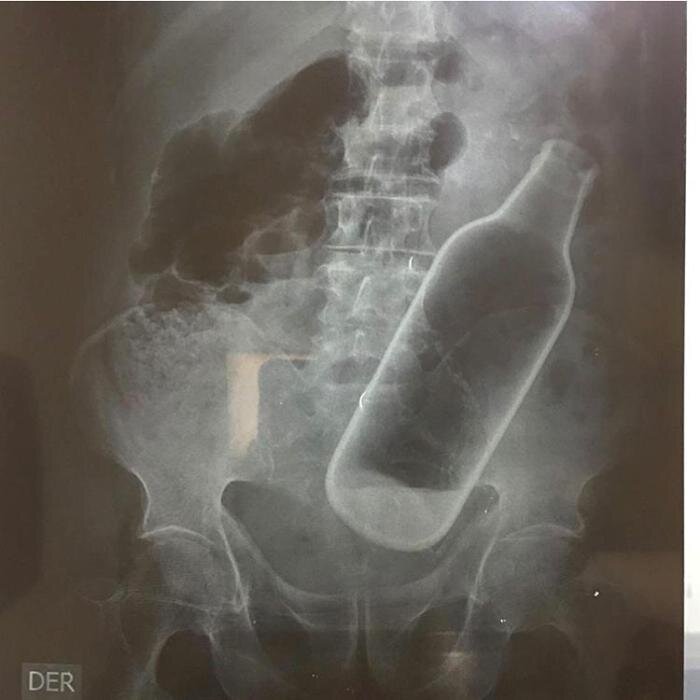

У китайца обнаружили бутылку в животе...

В китае мужчина обратился в больницу с жалобами на то,что ему тяжело ходить. Медики сделали рентген и были шокированы - внутрт пациаета была бутылка. Врачам пришлось немедленно оперировать мужчину,чтобы извлечь бутылку. Оперирование прошло успешно,бутылку достали... Пациет рассказал что бутылка оказалась в нем совершенно случайно.... Ахаха,прятал саке от жены походу... А как вы думаете,как она туда попала?!!

Рентген